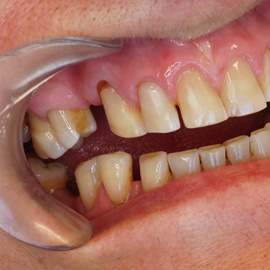

Wybielanie obejmujące pojedyncze zęby jest dość często spotykane. Najczęstszą przyczyną dyskoloracji zęba jest obumarcie miazgi i brak następowego poprawnego leczenia kanałowego, lub leczenie nieprawidłowe. Czasami udaje się przeprowadzić proces wybielania, który jest zadowalający dla pacjenta, a czasami w oparciu o uzyskany wynik można przeprowadzić leczenie protetyczne np. koroną lub licówką całoceramiczną.

Trzeba jednak uważać, ponieważ nieumiejętnie przeprowadzone wybielanie może być przyczyną resorpcji wewnętrznej i może sie skończyć utratą całego zęba...juz wybielonego. Poniżej zdjęcia przed i po leczeniu mikrochirurgicznym resorpcji.